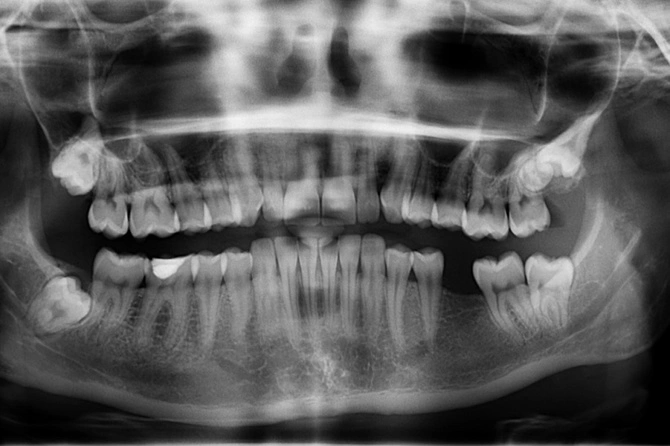

Врач-стоматолог, челюстно-лицевой хирург Екатерина Шаргородская рассказала о целой цепочке проблем со здоровьем, которые могут появиться только из-за одного выпавшего зуба. По ее словам, в этом случае нарушается работа всей челюстной системы.

«Отсутствие хотя бы одного зуба ведет к неправильному перевариванию пищи из-за того, что неправильно разжевывается пищевой комок. Из-за отсутствующего зуба у нас страдает и височно-нижнечелюстной сустав. Из-за этого могут появиться проблемы с ушами, например глухота, либо головные боли», — цитирует врача Москва 24.

В запущенных ситуациях развиваются болезни сердца, нарушается работа легких. Как пояснила стоматолог, недуги возникают из-за смещенных суставов.